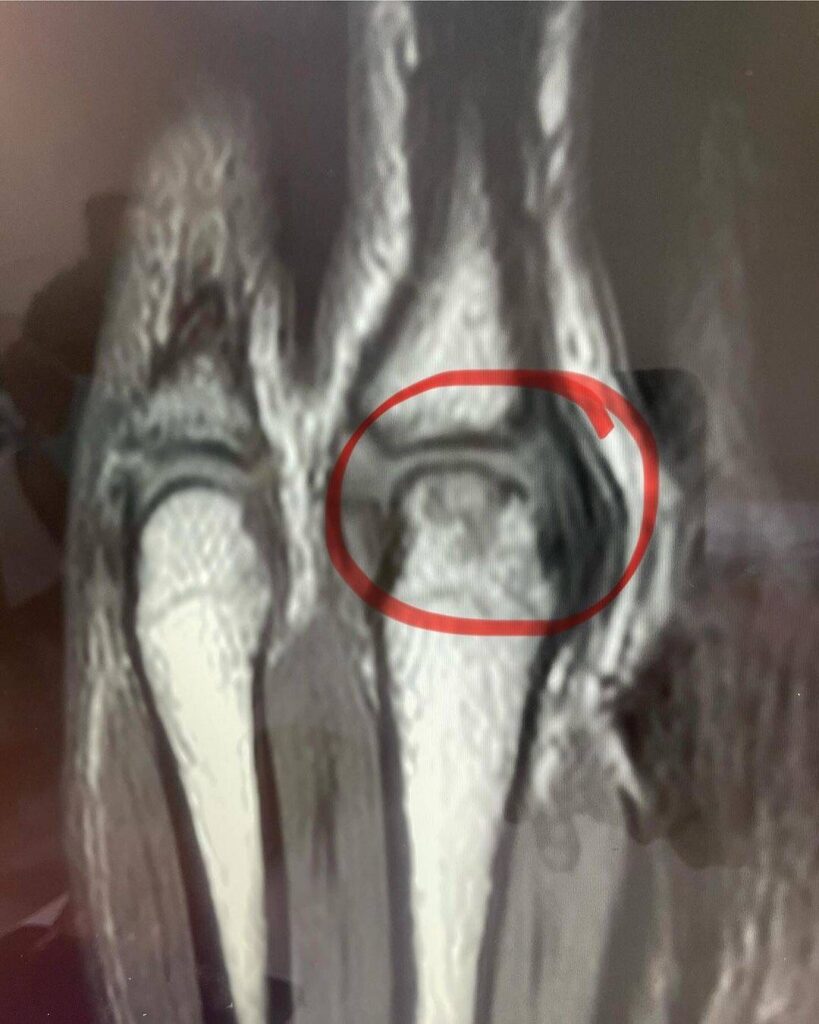

ล่าสุด แดเนียลก็ได้เผยออกมาแล้วว่าสาเหตุที่ตัวเขาหายหน้าหายตาไปเลยก็เพราะว่าเขาเพิ่งเข้ารับการผ่าตัดรักษามือนั่นเอง โดยตลอดระยะเวลากว่าหนึ่งปีที่ผ่านมา แดเนียลมีอาการบาดเจ็บที่มือมาโดยตลอดและมันก็ส่งผลกระทบต่อฟอร์มการชกของเขาอยู่ไม่น้อย ดังนั้นพอจบทัวร์นาเมนต์ RWS ซีซั่นสอง เขาก็เลยไม่รีรอที่จะรีบเข้ารับการผ่าตัดทันทีเลย